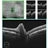

- Solitary NonSyndromatic Astrocytic Hemartoma of the Retina

- astrocytic hamartoma

- Optical coherence tomography system

- 66-year-old white male without history of tuberous sclerosis was found to have an incidental, asymptomatic, translucent, retinal lesion with a few small telangiectatic vessels within it. The FA showed early hyperFL of these small vessels with prominent late leakage/staining. The OCT showed a retinal mass with a "moth eaten" appearance. Vision was 20/20 and the rest of the exam was unremarkable.